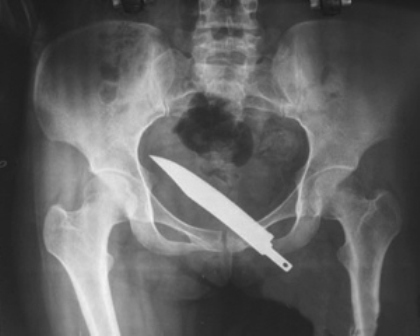

4个月前,施小姐遭歹徒抢劫,被刀刺伤。一把15厘米长的刀片深埋她体内,多家医院却未查出。前天,折磨她多月的刀片被取出。

在此后4个多月里,施小姐不仅疼痛加剧,还出现尿血症状。她辗转去了几家医院,但都被视作膀胱炎。前不久,她在安亭医院做X光检查,这才发现膀胱内竟有一把长15厘米、宽3厘米的刀片。

医生介绍说:“外伤在大腿根部,经过4个多月的肌肉运动,刀片在肌肉推动下缓慢进入腹腔和盆腔,造成慢性的膀胱出血。”